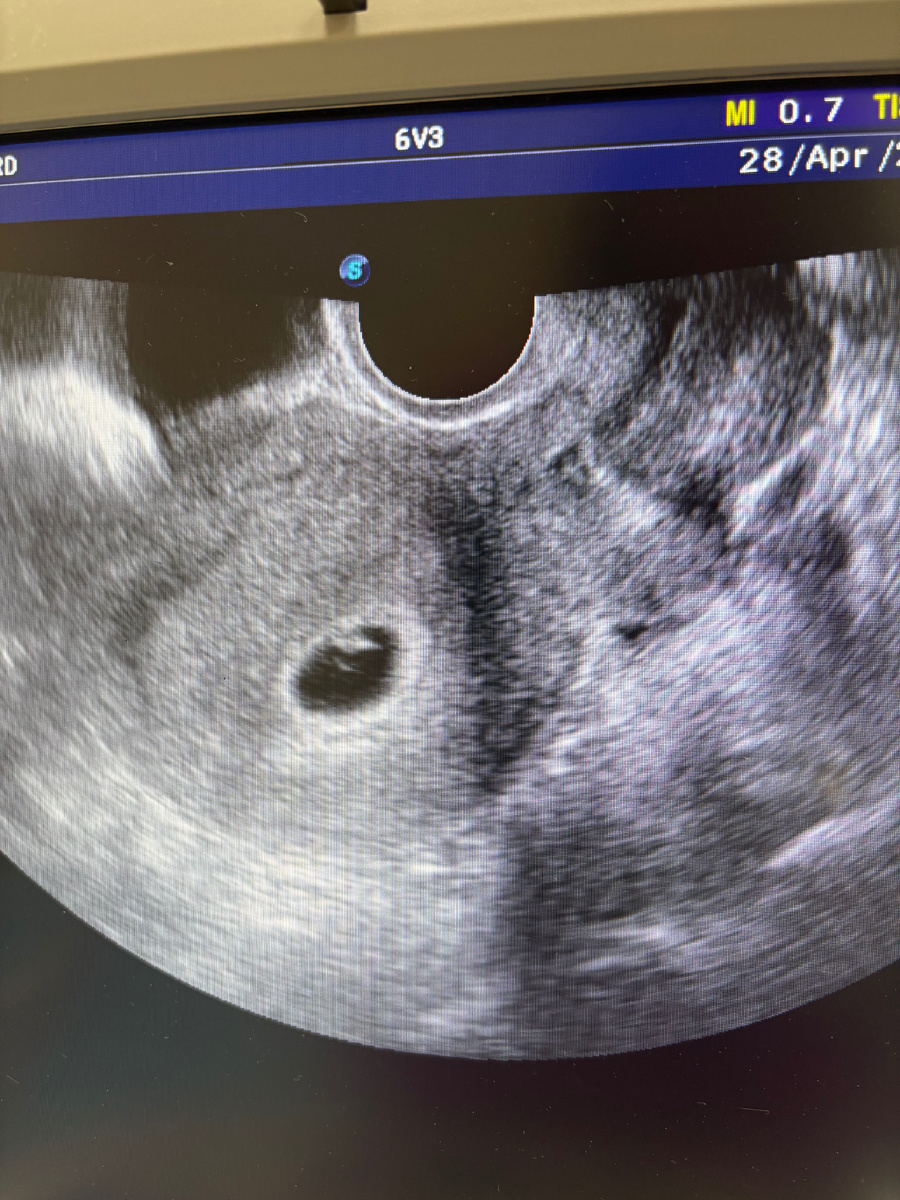

Синдром поликистозных яичников (СПКЯ) — это эндокринное нарушение, при котором не происходит овуляция и нарушен обмен веществ.